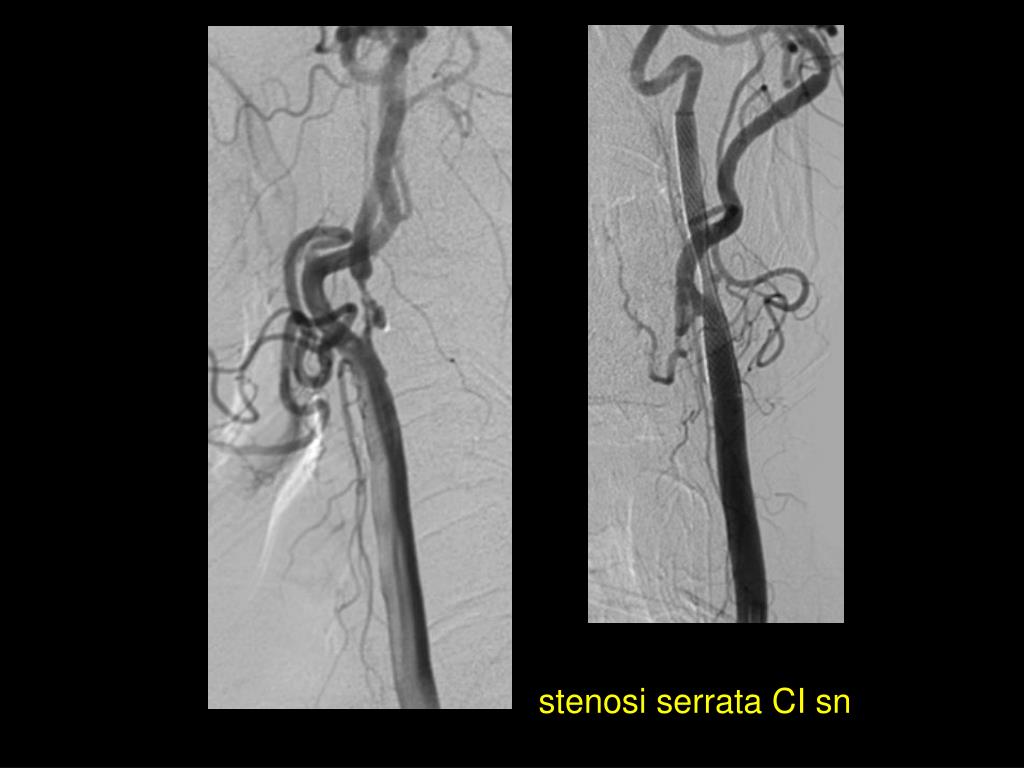

22. stenosi serrata CI sn

23. 3 giorni dopo 20 giorni dopo

34. Carotide interna sinistra